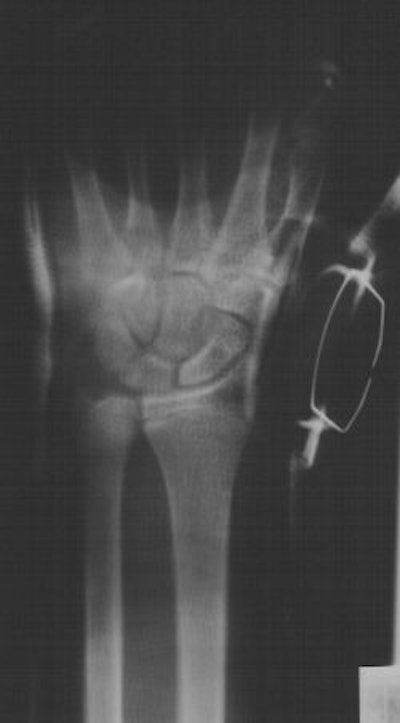

![]() |

| Twenty-five weeks post-injury and complete healing of scaphoid. Clinical images courtesy of Dr. Anthony Mauriello, Jr., MidState Orthopaedics, Lancaster, PA. |